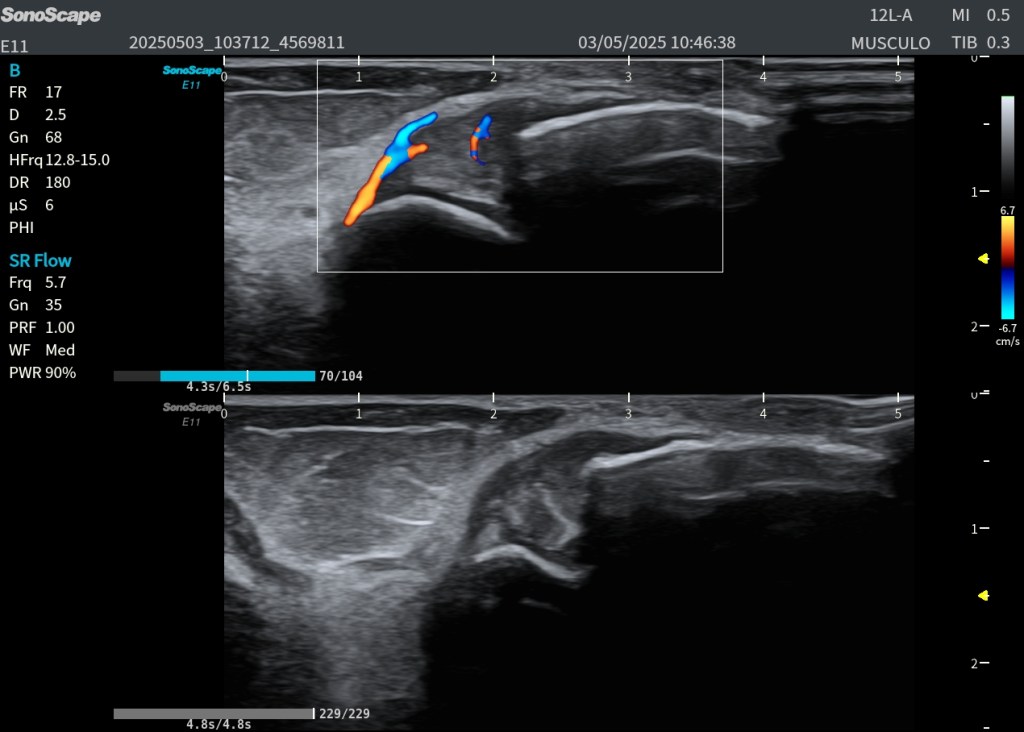

El estudio ecográfico longitudinal y transversal del compartimento posterior superficial muestra:

- Asincronía visible entre gastrocnemio y sóleo durante maniobras dinámicas de dorsiflexión y plantiflexión.

- Microvascularización intramuscular visible en modo Doppler en las fibras retraídas, indicativa de actividad reparativa.